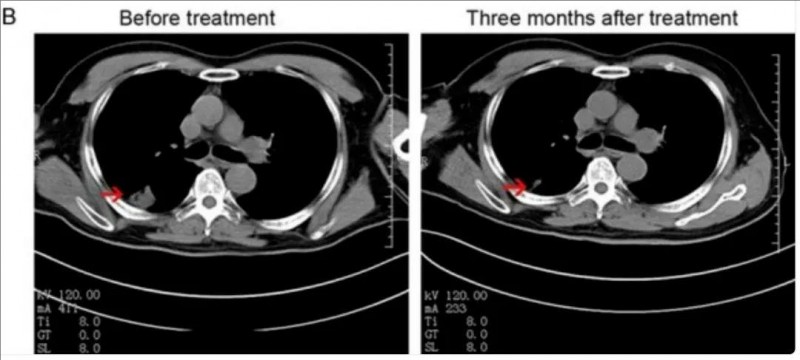

其中,NK细胞联合治疗组有一例IVA期非小细胞肺癌男性患者,在治疗3个月后,获得部分缓解(PR)。CT扫描显示:右肺肿瘤显著缩小,从3.5×3.5 cm(治疗前),缩小至1.7×1.3 cm(治疗后)。

▲图源“Am J Cancer Res”,版权归原作者所有,如无意中侵犯了知识产权,请联系我们删除